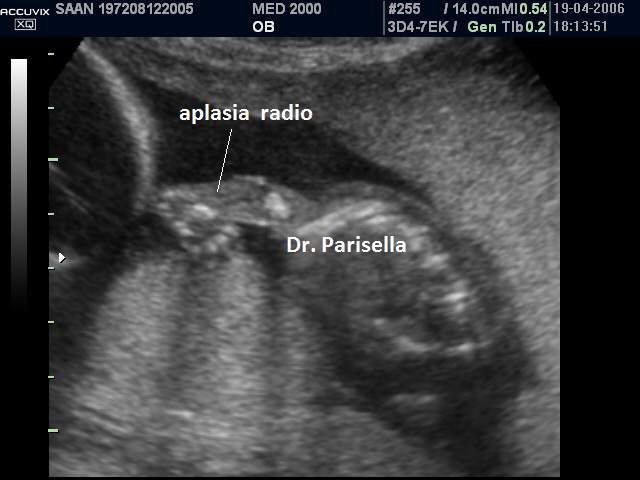

aplasia radio

La displasia boomerang รจ una sindrome estremamente rara caratterizzata da nanismo micromelico con arti ricurvi e rigidi, difetti di ossificazione, aplasia della fibula, aplasia del radio, facies caratteristica con radice del naso ampia ed ipoplasia delle narici e del setto nasale.